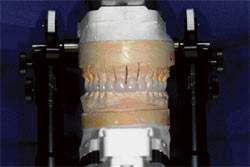

During the insertion appointment, the provisionals were removed, and the preparations were cleaned with hydrogen peroxide. The definitive restorations were tried for fit and then prepared for cementation (Figure 3). The definitive Captek restorations (Figure 4) would be conventionally cemented in the posterior region, thereby avoiding the need to perform isolation with a rubber dam. After the posterior restorations were cemented and cleaned of excess cement, the anterior segment was isolated with a rubber dam and the six porcelain laminate veneers were bonded in place with luting cement (Appeal+1, Ivoclar Vivadent) (Figure 5). After clean-up, the occlusion was checked, minor adjustments were made, and the restorations were polished (Figure 6). The patient was scheduled for a postoperative visit, at which time the occlusion was rechecked and the length and incisal edge position was verified phonetically (Figure 7A; Figure 7B; Figure 7C and Figure 8).

| Figure 3 Definitive restorations were prepared for cementation. | Figure 4 Captek restorations were cemented posteriorly. | |